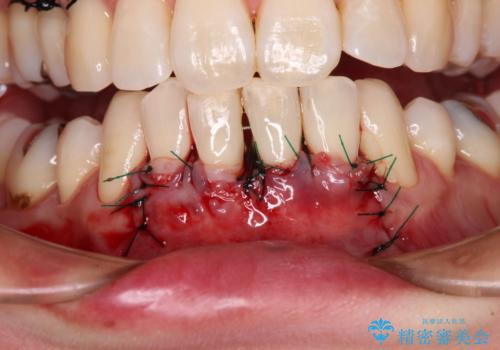

歯肉退縮に対して、上顎からの結合組織移植術(CTG)により、歯根の被覆を行うとともに、歯肉の厚みを増すことで将来の退縮リスクを抑制することとしました。

被覆量が不十分の場合には、追加で手術を行うことで患者様の了解を得ました。

歯と歯と歯肉の間にある三角形の隙間(ブラックトライアングル)は歯肉移植では改善できないため、根面被覆できる量に限界がありましたが、最大限回復させることができました。